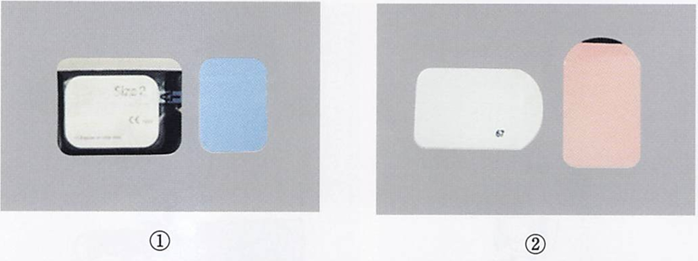

午前-50

59歳の女性。口渇感と舌の違和感を主訴として来院した。6か月前から自覚していたが様子をみていたところ、1か月前から水がないと食事がしにくくなったという。初診時の口腔内写真と検査に用いた器材の写真を別に示す。検査はどれか。1つ選べ。

a.味覚検査

b.ガムテスト

c.サクソンテスト

d.シルマーテスト

解答を見る

c